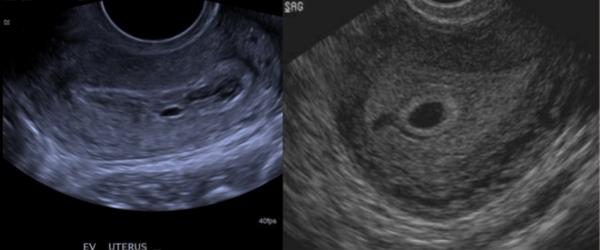

@majamat Ahoj. Pri zdravom tehotenstve je gestacny vak s hyperechogennym lemom("svieti")=choriove struktury, je ulozeny excentricky a ma pravidelny tvar. Pri mimomaternicovom sa moze vyskytnut pseudogestacny vak,ten naopak ten svetly vyrazny len nema,lebo sa nejedna o pravy vak,ide iba o akusi pseudodutinku s tekutinou. Prikladam foto. Prva GEU,druha zdrava incip.gravidita

@sabinka022 Ďakujem to moje sono vyzeralo presne ako ten druhý obrázok tak budem veriť že to bude v poriadku